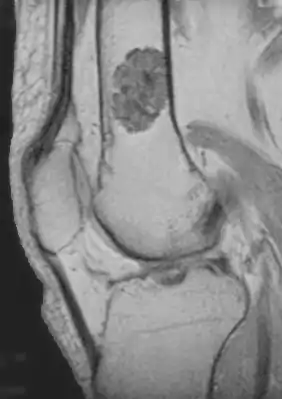

MRI T1 showing an enchondroma in the femur

Diagnosistic tests include medical imaging.[2] Appearances on X-ray show a small lobe-shaped, dark tumor in the middle of the bone.[2] It typically contains white spots; calcified chondroid matrix (a "rings and arcs" pattern of calcification).[2] It does not extend into soft tissues.[6] Magnetic resonance imaging (MRI) and CT scan may be requested to further evaluate the tumor.[8]